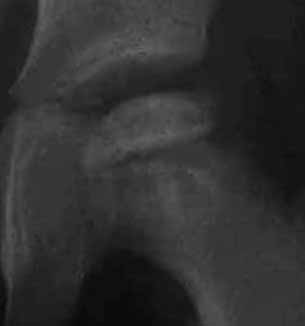

上図は10歳男子で、装具療法がうまくゆかないまま放置されていた例で、著しい変形があった例です。

左図は手術前です。骨頭の外側の1部が臼蓋からはみだしています。右図のように骨切りをおこなって、骨頭の向きを変え、はみだした部分までも完全に臼蓋の奥深くに包み込みます。この手術は術前に骨の正確な計測を行い、手術ではその計画を厳密に実行します。皮膚切開の後には、筋肉の剥離、骨の展開、関節包の温存、金属の打ち込む方向、注意深い骨切り、下肢短縮を最小限に押さえる工夫、など、いずれをとっても慣れた術者が行わないと(少なくとも50例の経験は必要)重篤な合併症をおこすことがあります。